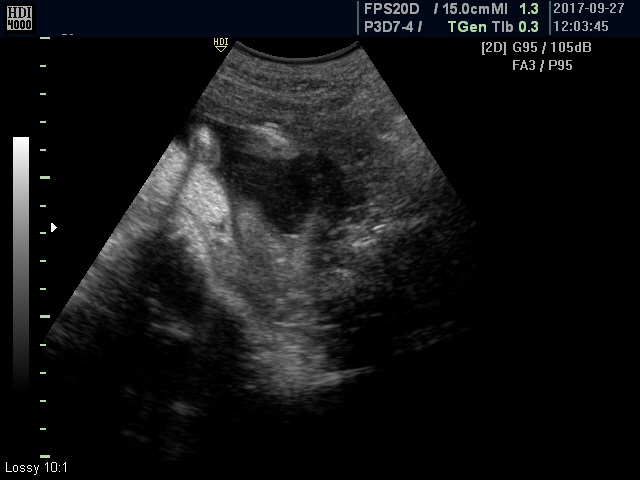

My doctor wasn't sure about the gender, and the picture is not the best, but maybe someone can help me. Doctor said maybe it's a girl.

That's a girl!